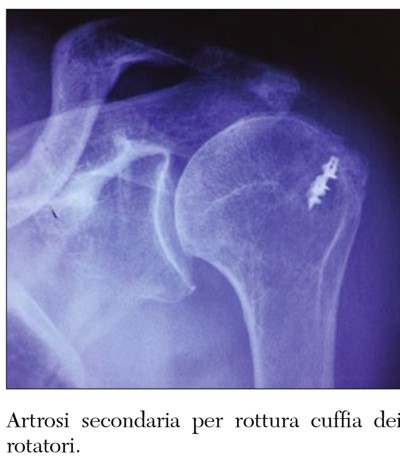

L’eziologia dell’artrosi può essere primaria oppure secondaria a traumi o fratture. Nelle fasi iniziali la cura è di tipo conservativo, gli obiettivi della fisioterapia sono di conservare e se possibile migliorare il movimento della spalla attraverso gli esercizi di stiramento e di rinforzo muscolare, mentre il dolore può essere controllato con la terapia fisica e con la terapia infiltrativa. Se queste cure non dovessero ridurre o eliminare il dolore la protesi rimane la soluzione definitiva.

L’usura articolare gioca un ruolo fondamentale nella comparsa dell’artrosi che rappresenta la principale causa di dolore e di perdita di movimento della spalla. Tale patologia è conseguente alla degenerazione dei tendini e della cartilagine. Clinicamente l’artrosi di spalla si presenta con scrosci articolari e con perdita progressiva del movimento di flessione, di abduzione e di extrarotazione.